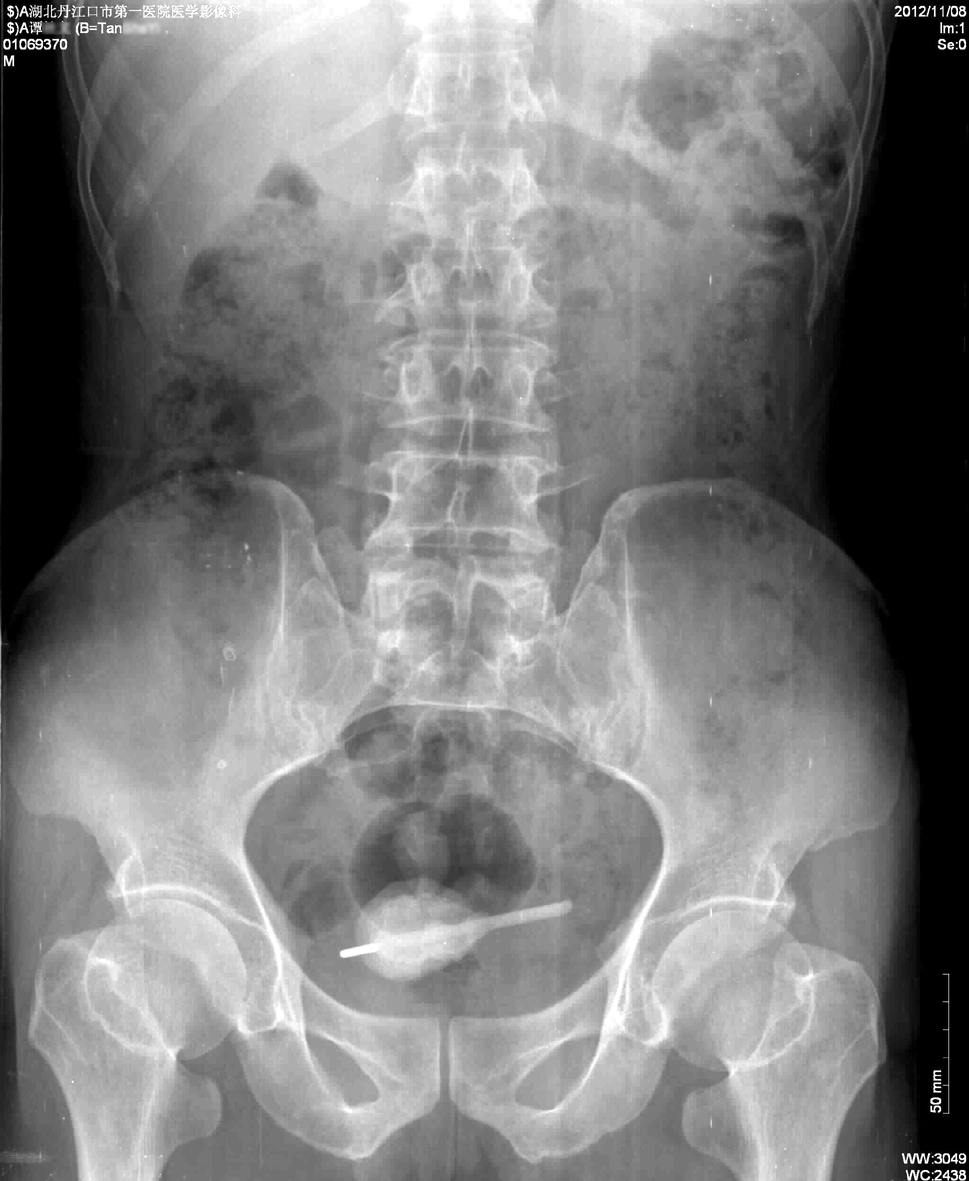

主治医师陈斌介绍:“男子一周前出现无明显诱因尿频、尿急、尿痛,伴发热,11月7日门诊以膀胱结石收入院,腹部拍片示膀胱异物,形似体温计(图一)。膀胱镜检查报告一长约6cm异物,外周结石包裹。”

图一:手术取出体温计

图二:腹部拍片